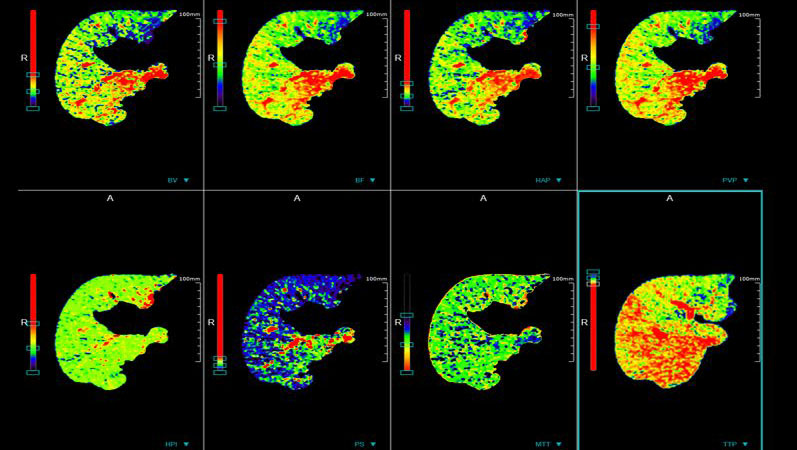

脑卒中中心

具备业内最便捷脑卒中解决方案,4D动态一站式卒中解决方案;一次对比剂注射即可获取脑动脉、脑静脉血管成像、CT灌注成像和 4D动态图像,助力脑卒中解决方案。使检查时间最短化,图像评估直观化,为抢救生命争分夺秒。

4D动态一站式卒中解决方案

颈脑动脉CTA+CTP

容积灌注成像

联影ct怎么样【小南快讯】辐射低、成像快、更精确!CT届的“天花板”——320排640层超高端CT落户奉中心!_https://www.jmylbn.com_新闻资讯_第21张